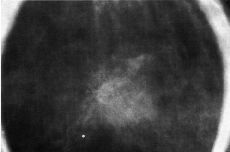

Mama Utilización de los criterios de la cicatriz radial en el diagnóstico diferencial de las lesiones estrelladas de la mama

Breast Utilization of radial scar criteria in the differential diagnosis of stellate breast lesions